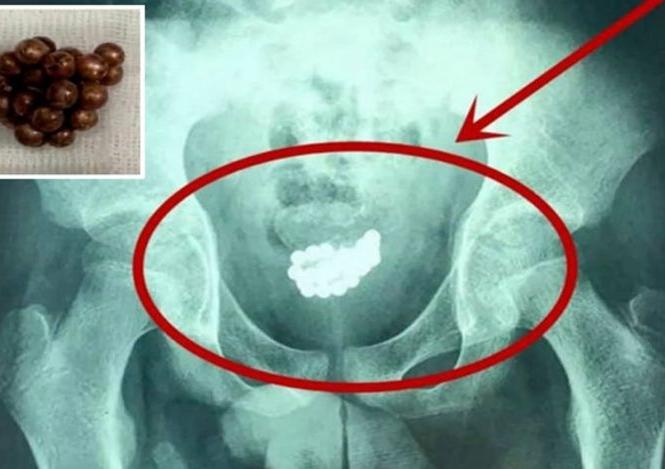

डॉक्टरांनी एका व्यक्तीच्या प्रायव्हेट पार्टमधून लोह चुंबकाची चेन काढली. यात २९ मॅग्नेटिक बॉल्स होते. डॉक्टरांनी फार मेहनतीनंतर या व्यक्तीच्या शरीरातून ही चेन बाहेर काढली.

ही घटना चीनच्या शांक्सीमधून समोर आली आहे. इथे राहणाऱ्या एका व्यक्तीला सीटी स्कॅननंतर लगेट हॉस्पिटलमध्ये भरती करण्यात आलं. कारण डॉक्टरांना सीटी स्कॅनमध्ये काही मॅग्नेटिक बॉल्स दिसले.

शांक्सीतील पीपल्स हॉस्पिटलमध्ये काम करणारे यूरोलॉजिस्ट क्यू ली मिंग यांनी एका न्यूज चॅनेलला दिलेल्या मुलाखतीत सांगितले की, या व्यक्तीच्या ब्लॅडरमध्ये अनेक मॅग्नेटिक बॉल्स होते.

हे बॉल्स सर्जरी करून बाहेर काढण्यात आलेत. डॉक्टरांना ब्लॅडरमधून हे मॅग्नेटिक बॉल्स बाहेर काढण्यासाठी बराच वेळ लागला.

हे मॅग्नेटिक बॉल्स आत टाकल्यावर १० दिवसांनी व्यक्तीच्या प्रायव्हेट पार्टमधून रक्त येत होतं. त्यानंतर तो लगेच हॉस्पिटलमध्ये गेला. तेव्हा डॉक्टरांना सीटी स्कॅनमध्ये हे बॉल्स दिसले.